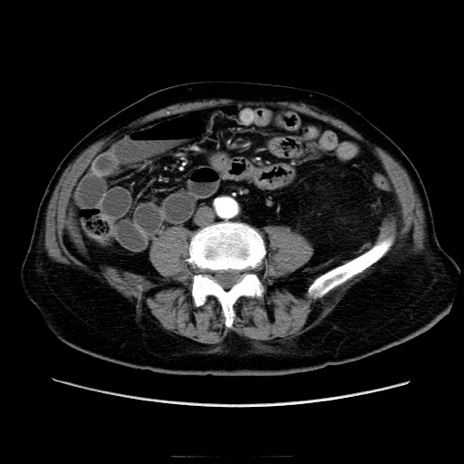

症例21(横断像)

【症例】70歳代男性

【主訴】腹痛

【現病歴】肝硬変・肝細胞癌にてかかりつけの方。約9時間前に食後より腹痛出現。症状が徐々に増悪し、嘔吐出現したため来院。

【既往歴】肝硬変、肝細胞癌(RFA、TACE後)

【身体所見】意識清明、表情苦悶様、BT 36℃、BP 129/78mmHg、P 88bpm、SpO2 97%(RA)、右上腹部から心窩部にかけて圧痛あり、反跳痛なし、筋性防御あり。

【データ】WBC 5800、CRP 0.16